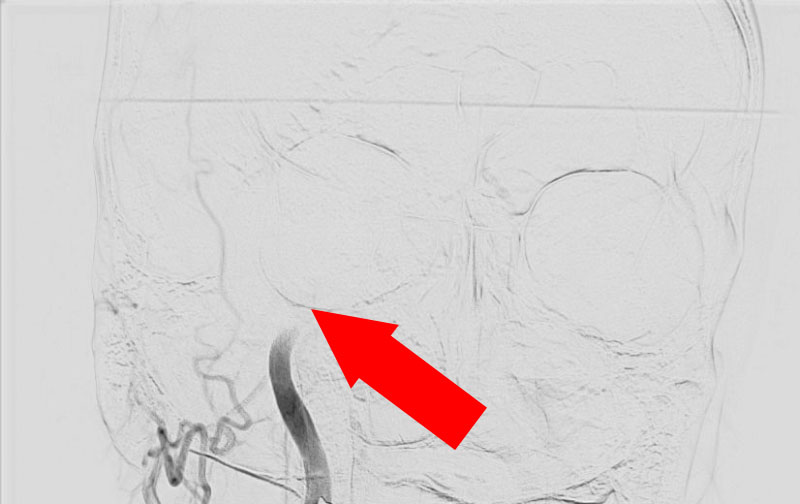

No.1267 手術中

左椎骨動脈瘤

50代

救急外来